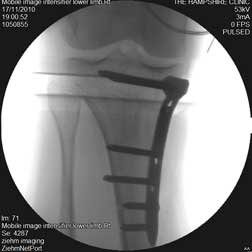

The next set of photos are of a young woman who has had a medial closing wedge osteotomy for lateral compartment disease only 3 weeks after the procedure was performed.

This last image shows the plate in place. Finally, there is a video to show the patient walking.